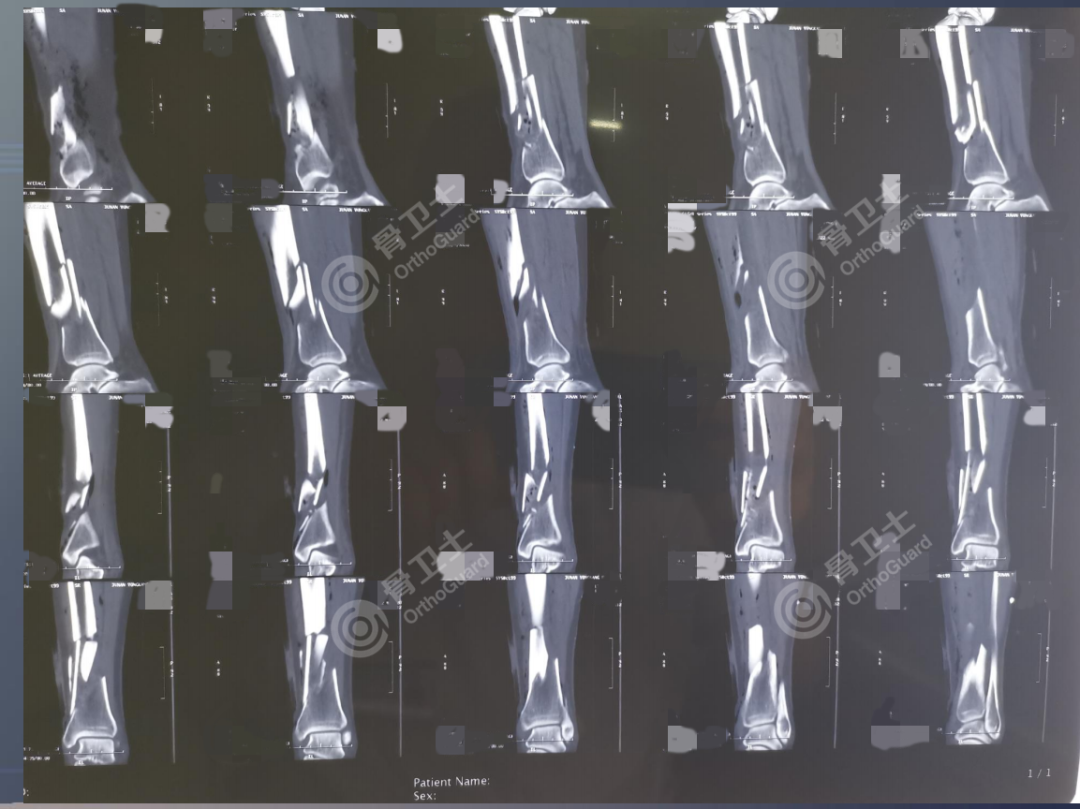

基本情况:女,56岁,因右小腿外伤后疼痛流血2小时入院。

查体:右侧小腿肿胀明显,右小腿中下端内侧见一直径约0.5cm皮肤伤口,流血,皮肤边缘整齐,污染轻,无张力性水泡,小腿中下1/3处及小腿上端外侧压痛明显,扪及骨擦感及异常活动,踝关节因疼痛活动受限,被动活动疼痛明显,无被动牵拉疼,足背动脉搏动正常,足趾感觉、活动正常。肢体远端血运未见异常。

诊断:右胫腓骨开放性骨折。

▲患者术前影像